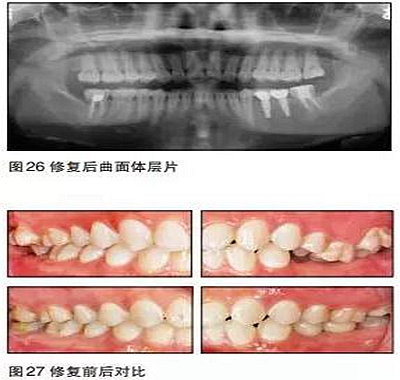

在本病例中,患者的主觀愿望是想通過(guò)種植來(lái)修復(fù)缺失牙??趦?nèi)檢查及口腔曲面體層片顯示患者缺牙區(qū)的骨質(zhì)良好,骨量充分,但咬合情況非常復(fù)雜。如果不先通過(guò)正畸治療來(lái)改善咬合而直接進(jìn)行種植手術(shù),那么后期的修復(fù)將異常困難。

本病例的難點(diǎn)在于如何創(chuàng)造適合種植的咬合條件。17、47、27、37正鎖,25、26過(guò)長(zhǎng)。傳統(tǒng)矯治正鎖時(shí)往往采用上下頜交互牽引的方式,但這種方法會(huì)導(dǎo)致磨牙不必要的伸長(zhǎng),且有明顯的疼痛感。本病例采用種植支抗釘技術(shù),在矯正17、47、27、37

正鎖的同時(shí)壓低相應(yīng)牙齒,在較短的時(shí)間內(nèi)完成了后牙鎖及伸長(zhǎng)牙的矯正,且患者感覺(jué)較為舒適。

35、36種植時(shí)采用骨水平的NobelActive植體;由于植體位置比較理想,修復(fù)體采用螺絲固位的氧化鋯基臺(tái)一體冠,便于今后牙冠及種植體的維護(hù)。最終種植修復(fù)完成后在咬合、美觀、牙齦乳頭充盈等方面都取得了滿意的效果。